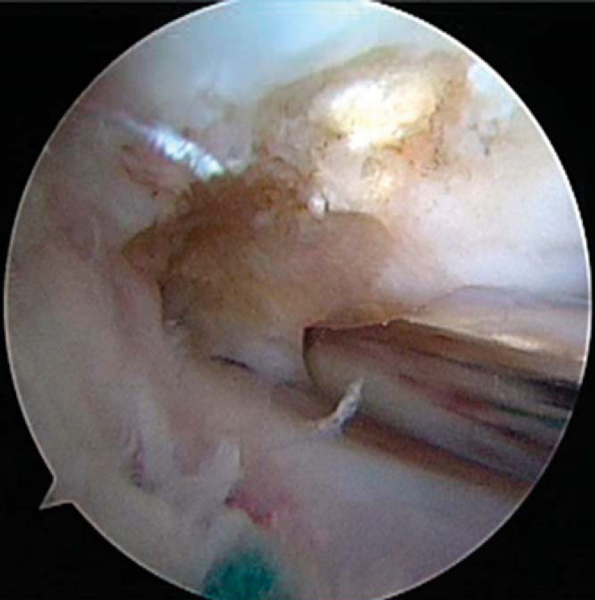

The extremity is prepared from the tourniquet distally with povidone-iodine (Betadine) and draped with a nonimpervious stockinette, half sheets, and an extremity drape. After a standard examination under anesthesia, any combined corrective osteotomies are performed first, followed by a standard diagnostic arthroscopy. Arthroscopy is performed by use of the standard anterolateral viewing portal, anteromedial instrumentation portal, and superomedial or superolateral outflow portal. Diagnostic arthroscopy is useful for confirming the diagnosis and also assessing the status of the articular cartilage. At our institution, the status of the cartilage is assessed preoperatively by cartilage-sensitive magnetic resonance imaging. Without these special sequences, it may be important to counsel the patient that the decision to proceed with meniscal transplantation is contingent on the suitability of the articular cartilage. After completion of the diagnostic arthroscopy, the meniscal remnant is débrided with a combination of arthroscopic baskets and motorized shavers, ideally leaving a cuff of 2 to 3 mm of native meniscus as a substrate for firm reattachment of the meniscal allograft (

Fig. 49-1

). The adjacent capsule and meniscal remnant are then rasped to stimulate bleeding for the reparative response. Notchplasty is then performed on the medial femoral condyle with a 4.5-mm motorized shaver, making sure that there is adequate arthroscopic access to the posterior horn of the meniscus for visualization and anatomic placement of the meniscal allograft (

Figure 49-1 |